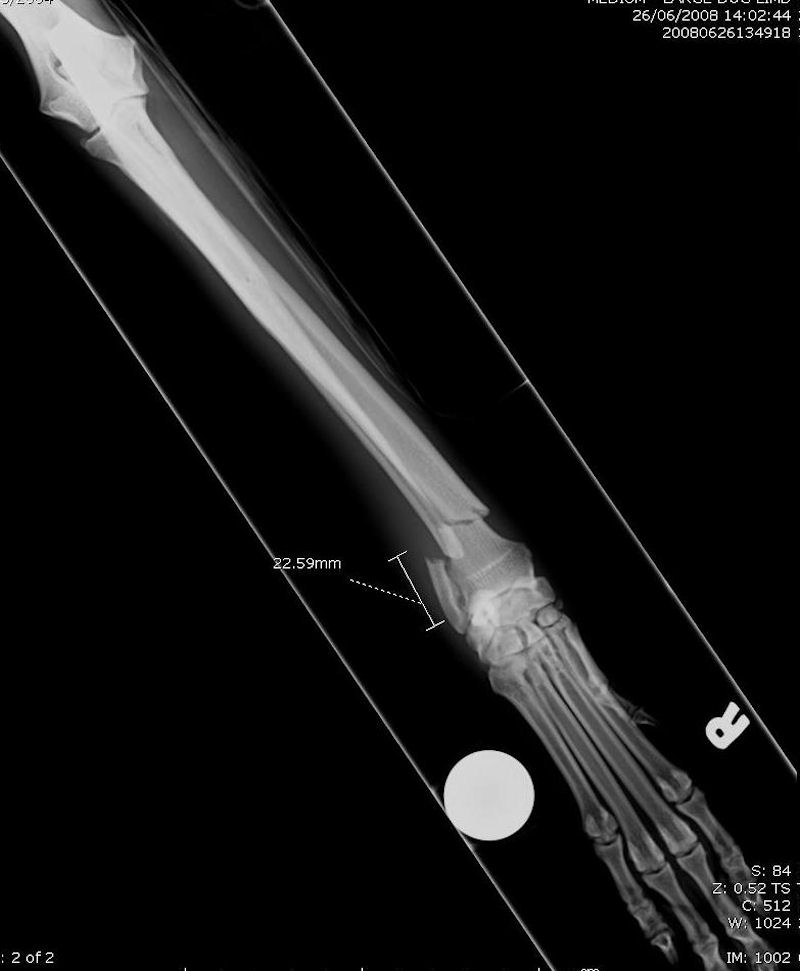

Dog X Ray Showing Radius and Ulna Fracture. Lateral View Stock Photo Radius/Ulna Fracture Dog Surgery Traumatic radius and ulna (antebrachial) fractures are common in dogs and cats and often require surgical treatment for optimal outcome (figure 14.1). This involves fracture near the bottom of the front limb, just above the carpus or. Result from falls and road accidents. Although various techniques can be used for the treatment of radius and ulna fractures in small breed. Radius/Ulna Fracture Dog Surgery.

Dog X Ray Showing Radius and Ulna Fracture. Cranial View Stock Photo Radius/Ulna Fracture Dog Surgery This involves fracture near the bottom of the front limb, just above the carpus or. What is radius/ulna repair surgery, and why does my pet need it? In an attempt to improve fracture management, künthscher established the foundations of minimally invasive fracture. Traumatic radius and ulna (antebrachial) fractures are common in dogs and cats and often require surgical treatment for. Radius/Ulna Fracture Dog Surgery.

Dog X Ray Showing Radius and Ulna Fracture. Cranial View Stock Image Radius/Ulna Fracture Dog Surgery Radius/ulna repair surgery is a surgical procedure performed to treat fractures or breaks in the radius and ulna bones of the. In an attempt to improve fracture management, künthscher established the foundations of minimally invasive fracture. What is radius/ulna repair surgery, and why does my pet need it? Fractures of the distal radius and ulna are common, especially in small. Radius/Ulna Fracture Dog Surgery.